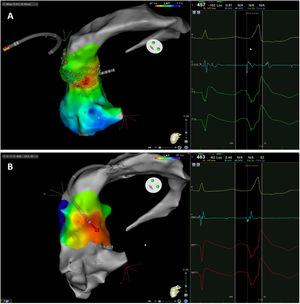

The mean number of points acquired with the PentaRay catheter was 507±213 before ablation during 15±10 min of mapping. In the first patient, who was undergoing a redo ablation of a PVC arising near the His bundle, mapping was carried out with the PentaRay in both the RVOT and the coronary cusps, particularly the non-coronary cusp (NCC) (Figure 2A). However, since the earliest activation site was located in the RVOT, with an optimal unipolar signal, ablation was performed there. In the other patients, the earliest LAT was located in the left coronary cusp (LCC) (n=3) – one in the LCC (Figure 3) and two beneath (Figure 2B), the papillary muscle (n=1), the aortic mitral continuity (AMC) (n=1) and the right (RCC)-NCC commissure (n=1). Median procedure and RF ablation times were 67±42 min and 294±112 s, respectively. Acute success was achieved in all patients (100%). Coronary angiography was performed in three patients – two cases of LCC PVCs and one with PVCs arising from the RCC-NCC commissure. In all patients, the coronary arteries were at a safe distance from the ablation catheter.

A. Premature ventricular contraction (PVC) activation map, projected in a posterior view, with the earliest activation point located in the right ventricular outflow tract (RVOT) slightly above the His bundle (5 mm away). This high-density activation mapping, performed with the PMF and the PentaRay mapping catheter, included 816 points (379 in the RVOT), resulting in a very detailed and accurate map. B. This high-density activation mapping included 308 points, with the earliest activation point just beneath the left coronary cusp. The figure is projected in the upper left posterior view. Also, in both maps performed with the PMF software and the PentaRay mapping catheter, the bipolar endocardial electrograms were less fractionated and had a higher voltage amplitude signal compared to the bipolar electrogram acquired with the ablation catheter, and so potentially more accurate. C. PVC activation map, projected in upper posterior view, with the earliest activation point in the aortomitral continuity. This activation map was performed with the standard approach and ST ablation catheter. Only 104 local activation time points were collected, since each point needs manual confirmation before validation and incorporation into the activation map, resulting in a less detailed map.

Premature ventricular contraction activation map, projected in an upper anterior view, with the earliest activation point located in the left coronary cusp. Both maps were performed in 12 minutes. A. This high-density activation map was produced with the PMF and the PentaRay catheter and included 547 points, resulting in a very detailed and accurate map. B. Standard activation map performed without PMF. Points were collected with the ablation catheter and required manual validation, resulting in fewer points being collected in the same amount of time – 42 points. Also, the bipolar endocardial electrogram had a lower voltage amplitude signal with larger electrogram duration compared to the bipolar electrogram acquired with the PentaRay catheter.